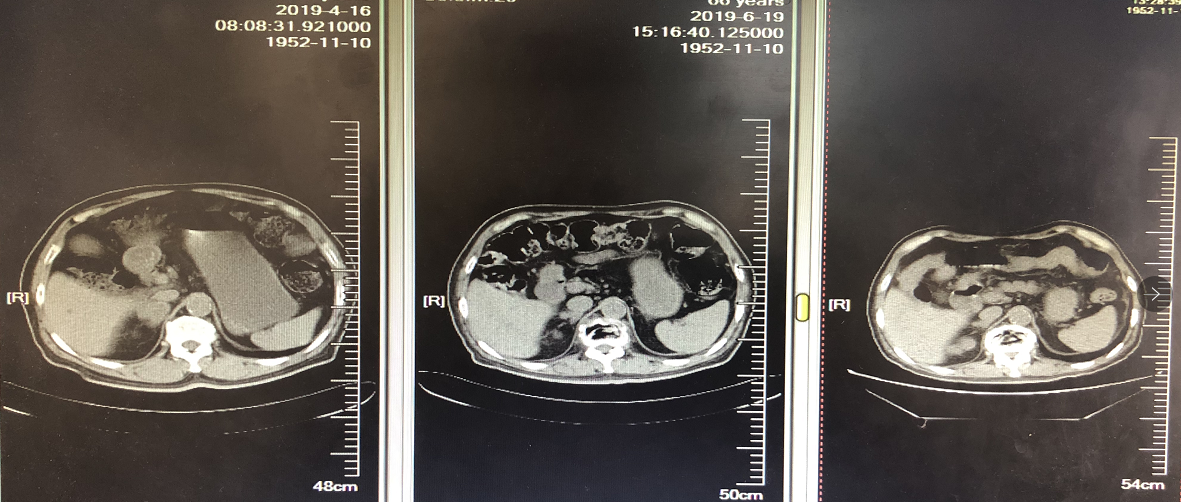

2019年5月更换为GP方案化疗,具体方案为吉西他滨1400mg + 顺铂 100mg x 1周期。同时接受唑来膦酸4mg x 1周期。化疗期间患者咳血胸闷加重,且周身乏力不适症状明显,急诊入院。1周期化疗后咳嗽咳血加重,腰部疼痛未缓解。复查胸部CT,右肺上叶病灶PD;右肾上腺病灶SD。患者对治疗耐受差,总体评价为PD。

图5. 二线化疗1周期后评估,右肺上叶病灶PD

图6. 二线化疗1周期后右肾上腺病灶评估SD

三线治疗前行基因检测,未观察到有意义的驱动突变,PD-L1高表达,>50%; TMB 高,为27.4Mut/Mb。与患者商量后,患者选择信迪利单抗。2019年5~6月接受三线信迪利单抗治疗,方案为信迪利单抗200mg,q21d x 3周期,同时接受唑来膦酸抗骨转移治疗。信迪利单抗治疗3周期后,咳嗽咳血基本消失,仍有腰部疼痛但较前减轻。对治疗耐受良好。复查胸腹部CT:肺部病灶明显缩小,右肾上腺病灶缩小,腰椎病灶变化缓解。目前,患者已经接受信迪利单抗注射液200mg单药治疗第八个周期,体能状态良好,病情改善明显。

图8. 信迪利单抗治疗3周期后肾上腺肿物缩小